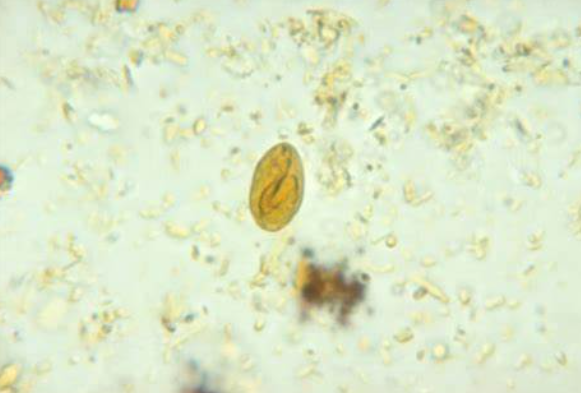

Giardia ở Chó (Giardia duodenalis) Giardia ở Chó là loài động vật nguyên sinh phổ biến ở chó và một loạt các vật chủ khác bao gồm mèo, gia súc, ngựa và người. Đường lây nhiễm chính là phân-miệng, thông qua tiếp xúc trực tiếp, gần gũi _ Ký sinh trùng: Giardia duodenalis (còn có […]

Sán lá Gan (Opisthorchis viverrini, Clonorchis sinensis)  Opisthorchis viverrini và Clonorchis sinensis là những loại sán lá của động vật ăn cá bao gồm chó, mèo và người ở Châu Á. Sá lá gan lây truyền sang người. – Ký sinh trùng: Opisthorchis viverrini, Clonorchis sinensis – Tên thường gọi: Sán lá gan […]